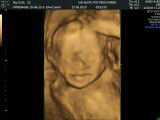

USG

Haii bunda.. Ini hasil USG kemarin waktu UK 22week ?? masih belum jelas bgt karena ketutup lendir lendir kata pak Dokternya. Share juga dong foto2 usg bunda semua ???